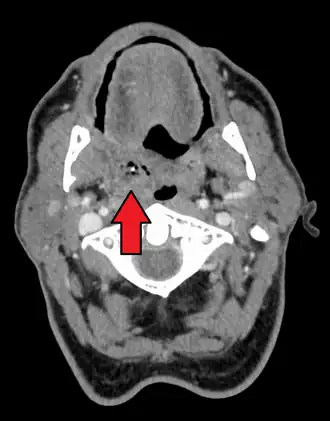

![]() | |

| Right-sided peritonsillar abscess | |